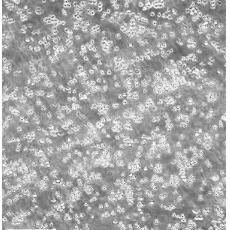

中文名稱(chēng) 人急性淋巴母細(xì)胞白血病細(xì)胞

組織來(lái)源 急性T淋巴細(xì)胞白血?。荒行?/td>

生長(zhǎng)特性 suspension

形態(tài)特征 lymphoblast

細(xì)胞描述 MOLT-4與MOLT-3來(lái)源于一名19歲的男性急性淋巴細(xì)胞性白血病的復(fù)發(fā)患者,該患者前期接受過(guò)多種藥物聯(lián)合化療。MOLT-4細(xì)胞系為T(mén)淋巴細(xì)胞起源,p53基因的第248位密碼子有一個(gè)G→A突變,不表達(dá)p53,不表達(dá)免疫球蛋白或EB病毒;可產(chǎn)生高水平的末端脫氧核糖轉(zhuǎn)移酶;表達(dá)CD1(49%),CD2(35%),CD3A(26%)B(33%)C(34%),CD4(55%),CD5(72%),CD6(22%),CD7(77%)。